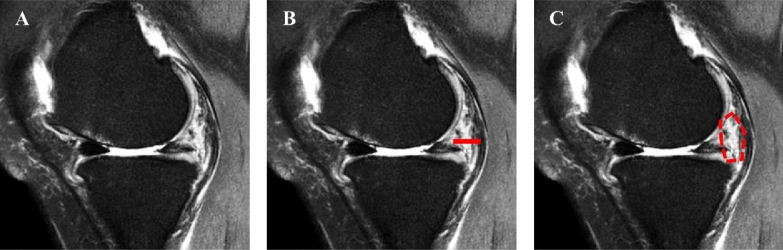

Methods: We retrospectively analyzed 60 patients who underwent medial unicompartmental knee arthroplasty (UKA) with positive (n = 20) and negative (n = 40) preoperative McMurray's tests. Preoperative magnetic resonance imaging (MRI), intraoperative gross morphology, and histological analysis of meniscus and synovium were evaluated to determine meniscal tears and perimeniscal synovitis. Univariate and multivariate regression analyses were done to determine the effects of meniscus tears and synovitis on McMurray's test results.

Results: Gross morphology of the medial meniscus (MM) showed 14 out of 20 torn menisci in the McMurray's (+) group compared with 22 out of 40 in the (-) group, with no difference in meniscus tear severity among groups. The (+) group showed higher values of synovial thickness (p < 0.001) and area (p < 0.001) compared with the (-) group on magnetic resonance imaging (MRI). Histological analysis showed higher synovitis (p < 0.001) scores and expression of inflammatory markers [interleukin (IL)-1β (p < 0.001), IL-6 (p = 0.007), nerve growth factor (NGF) (p = 0.003), inducible nitric oxide synthase (iNOS) (p < 0.001)] in the perimeniscal synovium of (+) group compared with the (-) group. Multivariable logistic analysis revealed that larger synovial area [odds ratio (OR) = 1.106, p = 0.008] and a higher histologic synovitis score (OR = 2.595, p = 0.011) were independently significant predictive factors for a positive McMurray's test.